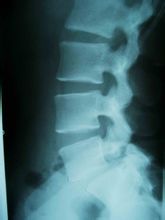

對於腰椎骨質增生,除了X片外,還有一些其他的診斷標準:

腰椎第二第三節增生1.腰痛,晨起重,活動後減輕;多活動或負重後腰痛又加重,以酸脹、不適為主;

6.X片顯示椎體有骨贅增生,椎間隙狹窄。